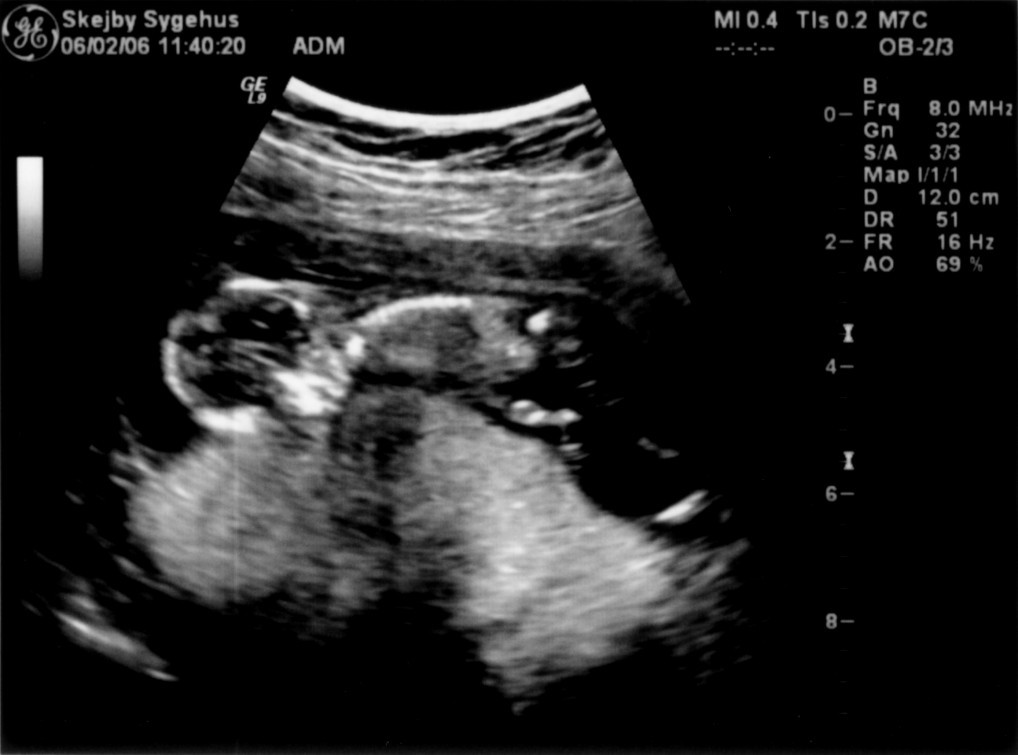

Ultralydsskanning den 22. marts 2006

Vi har så endelig været på Skejby Sygehus, hvor specialisterne skulle vurdere babys hjerte. Konklussionen var at baby og hendes hjerte ikke fejler noget - alt er i den skønneste orden. Der blev foretaget en meget grundig skanning og billederne blev vurderet af en afdelingslæge, en overlæge samt en overlæge med mange års international erfaring i børns hjertefejl. Det var en stor lettelse at hun ikke fejler noget. Baby blev undersøgt generelt en gang til at specialisterne og alt er som det skal være. De kunne desuden konstatere, at det er en pige... Du kan se de billeder vi fik fra skanningen herunder.

Baby ligger med hovedet nederst i midten og kigger op. Hun flekser så meget i ryggen at hendes ben går helt op over hovedet. Babys hjerte med nogle målinger.